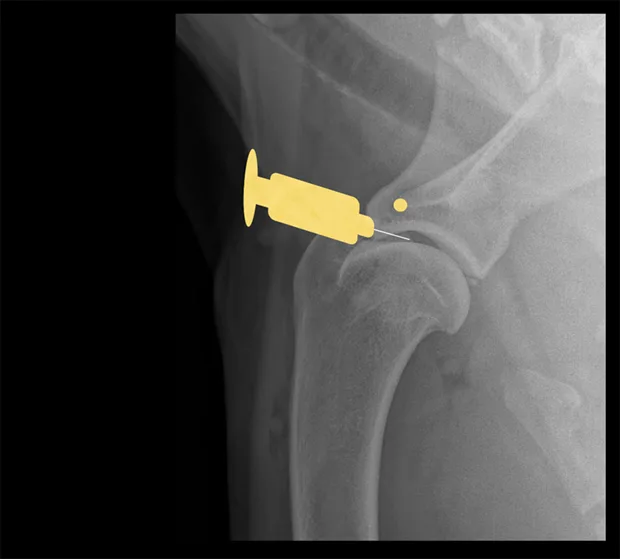

Hip

Lateral view of pelvis. Insert the needle at the proximal extent of the greater trochanter into the hip joint in a lateral-to-medial direction.